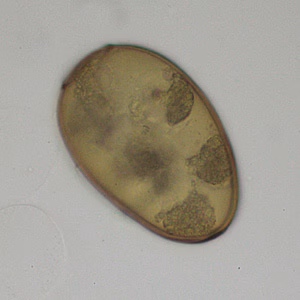

A 26-year-old female presented at a local hospital with severe pain and bloody discharge from the ear. The symptoms started while on a returning flight from vacation in Central America. The patient explained that while on vacation she visited a local physician to have a fly removed from her ear canal.